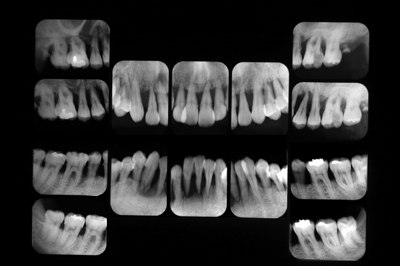

下顎前歯に注目ください。左:初診時、根尖を超えて骨がないようにみえますが 右:一年後。

この間、防カビ剤なんて怪しげな薬はもちろん、特殊なメンブレン何も使っていません。私たちが使っているのは患者さん自身の歯ブラシと、卒直後のコンビニ美容歯科医さんたちが「凶器」とホームページに書いているよくシャープ二ングしたスケーラーのみです。